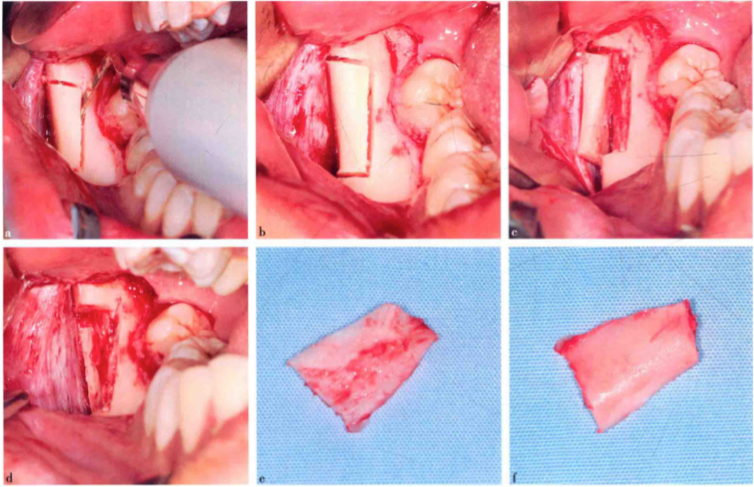

STEP 4:植骨

1、移植骨块的稳定固定以及与植骨床密切贴合是保证移植骨块愈合的基本条件。

放置骨块前,先对受骨床和骨块进行外形预备,适当调整,使二者能较好的贴合,受区处理主要包括以下几方面:

①清除受植区骨面的肉芽组织和结缔组织;

②开放部分髓腔,加速移植骨块的再血管化;

③修整骨面外形,使骨块与之紧密接触并增大接触面积;

④存在邻牙时,注意保护邻面牙槽嵴。

骨块修整

去皮质化

2、在植骨前需在移植骨块上预备螺丝通道,此通道直径应略大于固定钛钉的直径,以较少钛钉旋转就位时对骨块的受力,防止造成骨块的破坏;同时需要在受植床上预备螺丝通道,此通道的直径应略小于钛钉直径,预备深度小于固位深度,以保证钛钉就位后有足够的固位力,形成良好的固位稳定,此预备法也被称为有限预备。

3、钛钉的选择数目:1个或2个直径:多为1.5mm长度:颊舌向固定时,钛钉长度=骨块厚度+受区厚度,钛钉尾部最好穿入或穿出对侧骨皮质;冠根向固定时,应保证钛钉在基骨内有足够长度

钛钉固定骨块